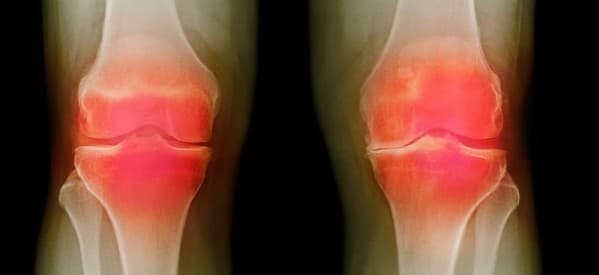

Khớp bị thoái hóa thường có các dấu hiệu nhận biết, như: Khớp kêu lạo xạo, lục cục mỗi khi co duỗi; cứng khớp vào buổi sáng khi mới thức dậy; khó vận động các khớp; đi lại khập khiễng do đau khớp háng; khó cử động cổ, đau mỏi vùng sau gáy lan đến cánh tay; tay không cầm nắm được; khớp còn bị đau khi vận động nhiều và giảm dần khi nghỉ ngơi; người bệnh đau khi ngồi xổm, leo cầu thang, đứng dậy khó khăn…

Khớp đau nhiều khi tăng cân do trọng lượng cơ thể gây áp lực lên các khớp. Thông thường, người bệnh bị đau đặc biệt tại khớp gối,khớp háng, khớp gót chân.

Khớp tê, sưng, biến dạng, teo ổ khớp… là những dấu hiệu chứng tỏ sụn khớp bị tổn thương nghiêm trọng.

Thoái hóa khớp là bệnh của toàn bộ các thành phần cấu tạo khớp như sụn khớp, xương dưới sụn, bao hoạt tích, bao khớp… Bệnh thường xảy ra ở các khớp chịu lực nhiều như: Cột sống, đầu gối, gót chân. Tình trạng này xảy ra do sự mất quân bình giữa sự tái tạo sụn và sự thoái hóa sụn.